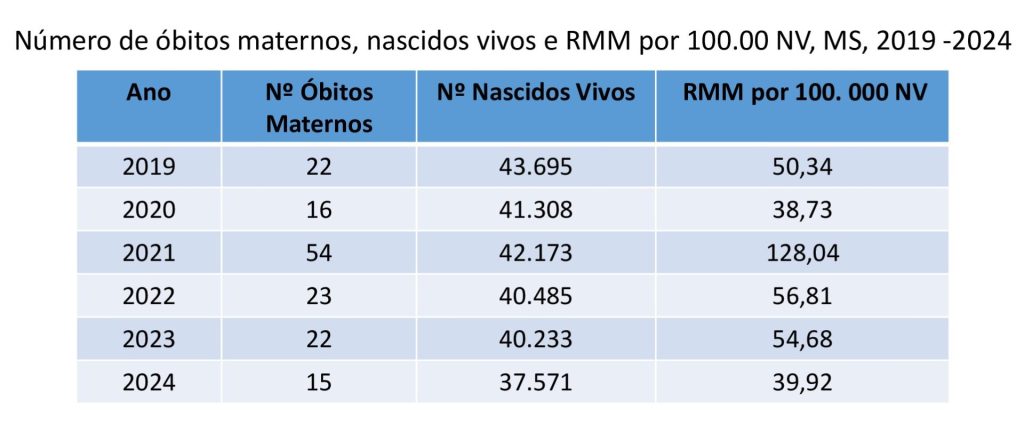

Nos últimos cincos anos o Estado implementou políticas públicas de saúde que permitiram uma redução significativa nas mortes de mulheres durante a gravidez ou até os 42 dias seguintes ao parto. Com exceção do ano de 2021, que por conta da pandemia de Covid houve um aumento da mortalidade, a queda no número de mortes é significativa conforme mostra a tabela abaixo.